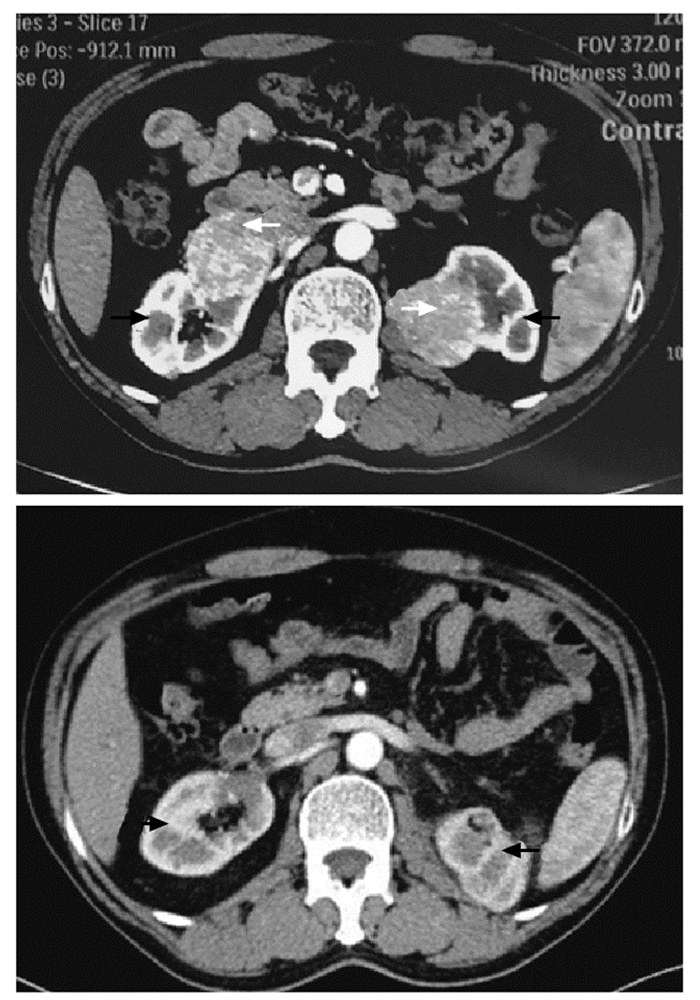

结果   14例AML患者中有1例相对孤立肾合并AML、7例多发AML、8例巨大AML(肿瘤最大直径>7 cm)、6例紧邻肾集合系统或肾门的AML以及2例合并出血破裂史AML, 病情复杂, 手术难度大。采取经腹腔镜或开放肾部分切除或肿瘤剜除术后, 顺利切除肿瘤, 病理检查提示肾AML, 术后定期门诊随访, 行CT扫描均无复发。全部患者术后肾功能保持良好, 术前和术后1个月血肌酐水平分别为(84.1±26.8)μg/ml和(97.5±37.0)μg/ml, 两组数据差异无统计学意义(t=-3.193, P>0.05)。

Results  Among 14 patients with renal AML, 1 had a relative solitary kidney with AML, 7 had multiple AML, 8 had huge AML (the maximum diameter of the tumor >7 cm), 6 had AML adjacent to the renal collection system or the renal portal, and 2 had AML combined with bleeding and rupture history; all cases were complicated and difficult to treat. All operations were successfully performed by laparoscopic or open partial nephrectomy or enucleation of the tumor, and pathological examination indicated renal AML. All patients were regularly followed up and no recurrence was found by CT scanning. The renal function of all patients was well preserved; the concentration of serum creatinine before and 1 month after the operation were (84.1±26.8)μg/ml and (97.5±37.0)μg/ml respectively, without statistically insignificant difference (t=-3.193, P>0.05).